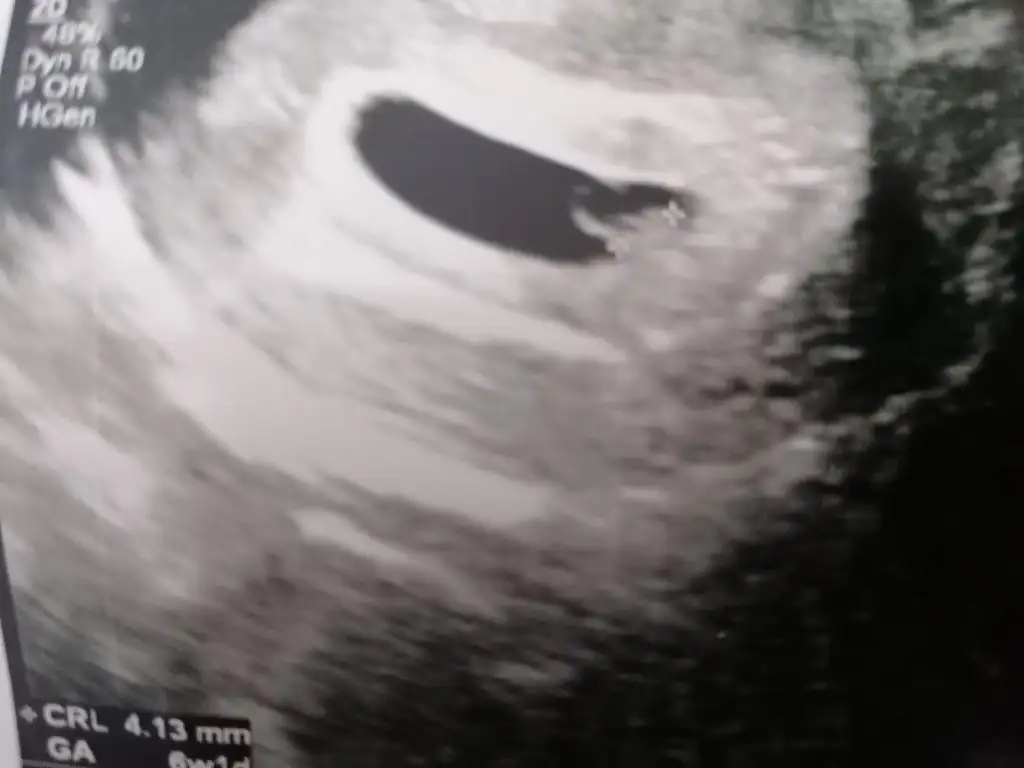

Kızlar vajinal ultrasondan cinsiyet tahmini yapabilecek var mı? Sanki konumu erkek gibi de bu yüzde kaç tutuyordu? ben hep kız hissediyorum, belki istediğim içindir. (önce sağlık sağlık sağlık tabiki si)

• IMG_20210202_213614.webp

15,6 KB · Görüntüleme: 66